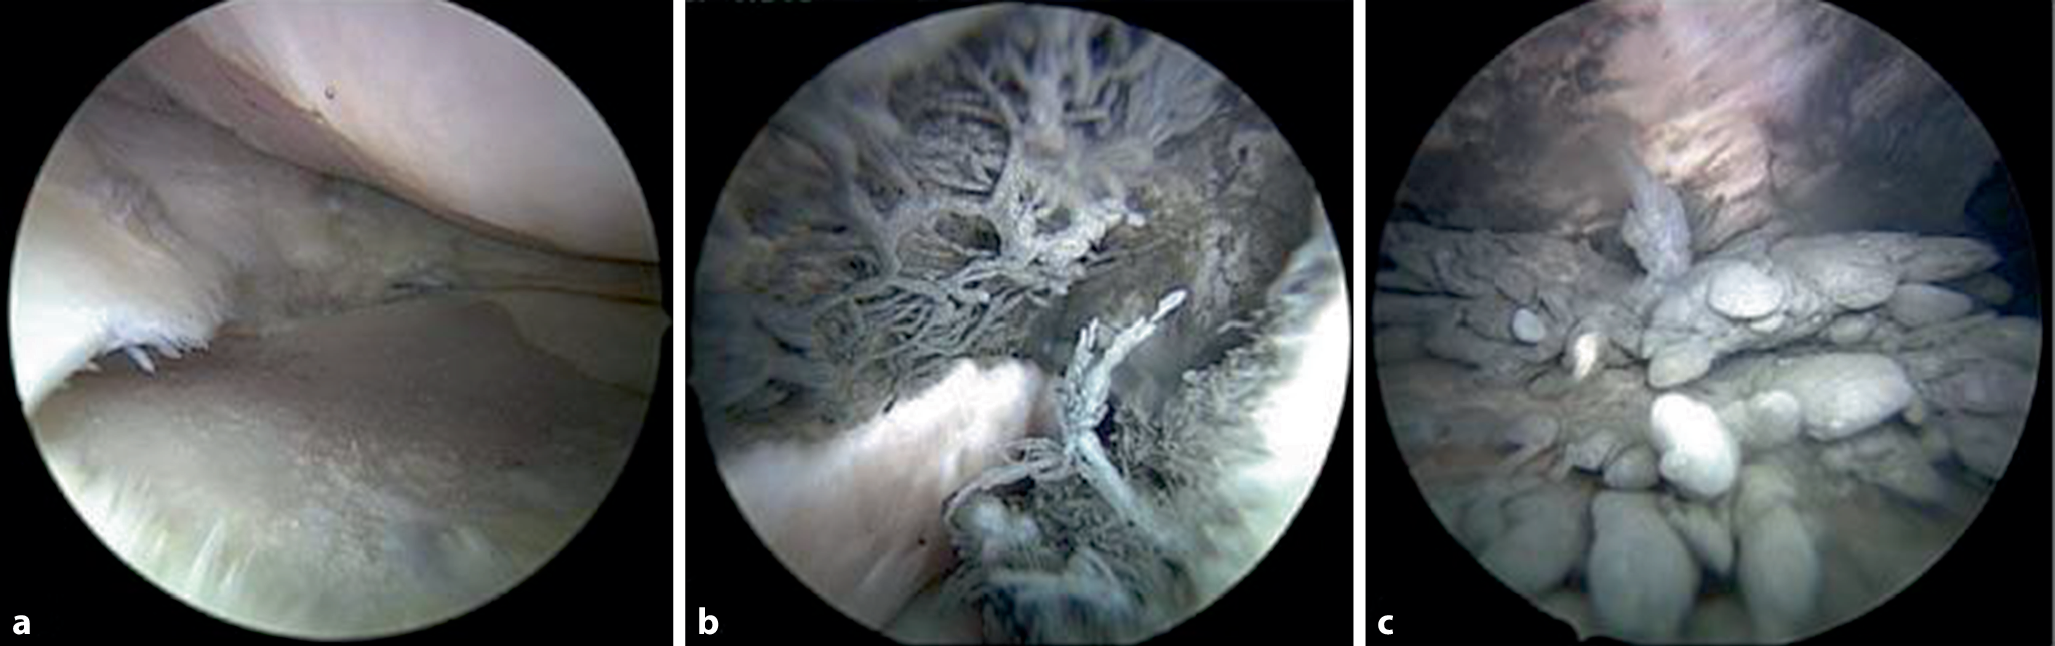

Als erster Schritt erfolgte die diagnostische Kniearthroskopie. Intraartikulär zeigte sich eine ausgeprägte, ubiquitäre Synovitis und Metallose (Abb. 3b und c) ohne Anhalt einer Penetration der Gelenkkapsel oder intraartikulären Materiallage. Im medialen Gelenkkompartiment zeigte sich eine großflächige Chondropathie IIIc° (klassifiziert nach der International Cartilage Research Society [ICRS]) femoral und korrespondierend dazu tibial mit einer Fläche von 30 × 40 mm (Abb. 3a). Auch im lateralen tibiofemoralen Kompartiment ließ sich tibial eine Chondropathie IIIc° nach ICRS von 20 × 25 mm nachweisen. Passend zur fortgeschrittenen Chondropathie waren große osteophytäre Randanbauten der Femurkondylen medial und lateral sichtbar. Der noch vorhandene Innenmeniskus zeigte komplexe degenerative Veränderungen mit aufgefaserten Meniskusrändern und einer Aufweichung des Meniskusgewebes. Es wurden Biopsien zur histopathologischen Untersuchung entnommen. Anschließend wurde das Implantat offen durch jeweils zwei 3 cm lange, longitudinale Hautschnitte durch die alten Narben, je über dem femoralen und tibialen Anteil der Verankerung, vollständig entfernt. Auch hier zeigte sich eine ausgeprägte Metallose. Abb. 4a zeigt den Operationssitus mit noch vollständig einliegendem Implantat und deutlich sichtbarer Metallose des umgebenen Weichteilgewebes. Die histopathologische Untersuchung konnte deutliche Metallabriebpartikel im Gewebe nachweisen (Abb. 5). Nach Explantation des Systems wurde ein Bruch der gelenkübergreifenden Feder festgestellt (Abb. 4a), was in den präoperativen radiologischen Bildern nicht sicher identifiziert werden konnte.

Abb. 3

a Arthroskopisches Bild der fortgeschrittenen Chondropathie IIIc° nach ICRS im medialen tibiofemoralen Kompartiment. b Ausgeprägte Synovitis im Recessus lateralis. c Metallinduzierte Synovitis im Recessus suprapatellaris